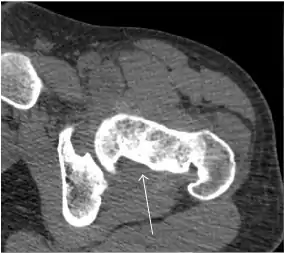

Synovial chondromatosis can be confidently diagnosed by X-ray when calcified cartilaginous chondromas are seen. However, other synovial proliferative processes, such as pigmented villonodular synovitis, require MRI for accurate diagnosis, although noncalcified synovitis can be suspected in radiographs by indirect signs, such as soft tissue swelling and/or erosions in the femoral head, femoral neck, or acetabulum (Figure 7).[1]

Figure 7:

Axial CT image of pigmented villonodular synovitis eroding the posterior cortex of the femoral neck.[1]

Sagittal T2* gradient echo image showing a posterior soft tissue mass with hypointense areas secondary to hemosiderin deposition.[1]

X-ray of synovial chondromatosis.[1]

CT of synovial chondromatosis.[1]

In synovial proliferative disorders, MRI demonstrates synovial hypertrophy. In the case of PVNS, characteristic foci of low signal intensity related to hemosiderin deposition are better seen on gradient echo T2* images (Figure 7). In the case of synovial osteochondromatosis, the synovial hypertrophy is accompanied by intermediate signal cartilaginous loose bodies and/or low signal calcified loose bodies.[1]